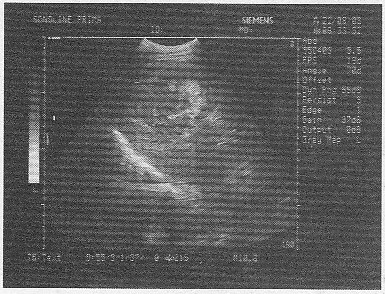

5.某患者25歲,高熱,肝區疼痛。肝臟聲像圖表現如圖,結合病史,最可能的診斷是

A.肝血管瘤

B.肝膿腫

C.肝硬化

D.肝癌

E.肝囊腫

正確答案:B 解題思路:高熱,肝區疼痛,聲像圖顯示肝內可見一無回聲暗區,壁厚,內部回聲不均勻。